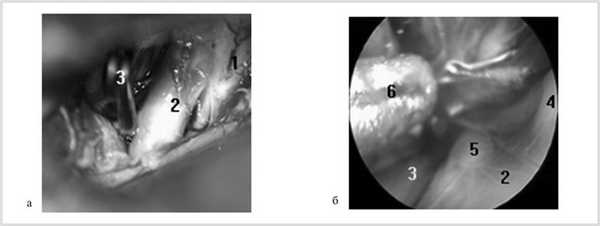

Рис. 1. Клипирование аневризмы левой внутренней сонной артерии (ВСА) из левостороннего птерионального доступа. а — вид через микроскоп после клипирования аневризмы хориоидального сегмента левой ВСА; б — вид через эндоскоп с тубусом 30° из ретрокаротидного промежутка. 1 — левый зрительный нерв, 2 — левая ВСА, 3 — клипса на шейке аневризмы, 4 — устье задней соединительной артерии, 5 — устье передней ворсинчатой артерии, 6 — наконечник аспиратора.

В большинстве наблюдений (у 32 из 38 больных) при АА офтальмического, коммуникантного и хориоидального сегментов ВСА ВЭСА на этапе арахноидальной диссекции и выделения аневризмы была эффективна для осмотра нижней поверхности ВСА, определения расположения устьев задней соединительной артерии (зСоА) и передней ворсинчатой артерии (ПВА), уточнения формы АА и возможности ее клипирования. После клипирования аневризмы ВЭСА позволяла исключить компрессию ветвей ВСА и удостовериться в полном перекрытии шейки аневризмы браншами клипсы (рис. 1, 2).